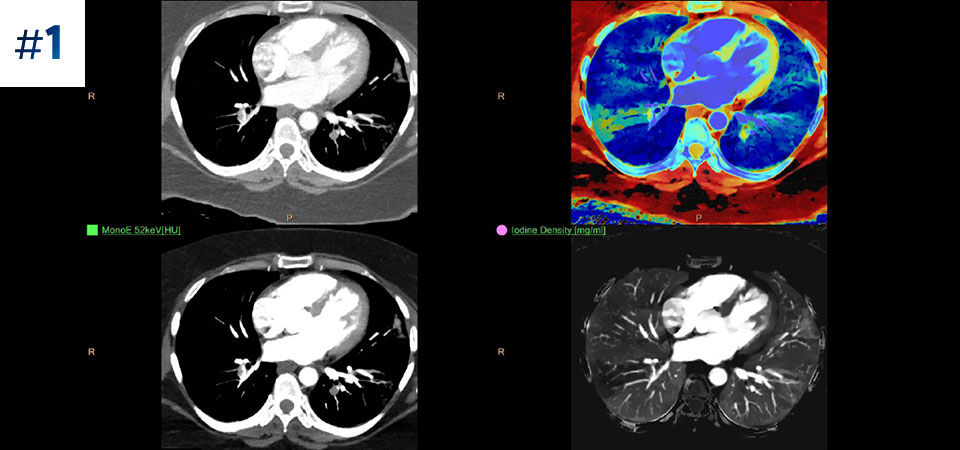

Go beyond conventional CT. See how layers of spectral-detector results can enhance your diagnostic confidence.

See the difference between spectral-detector CT and conventional CT